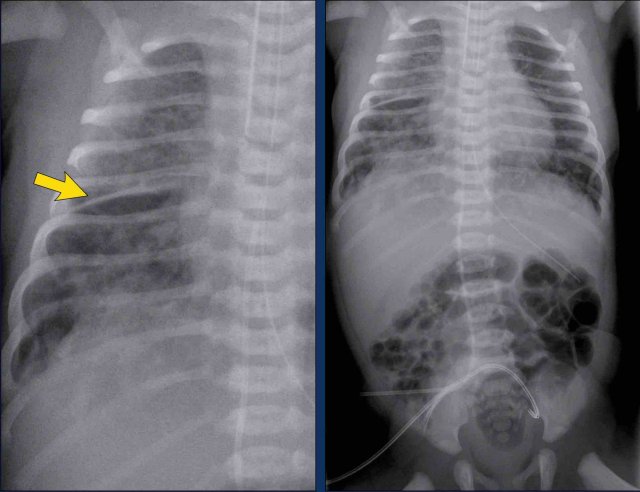

29 weeks + 1, day one. CPAP.

Findings:

• Reticulogranular opacification of lungs

• Air bronchogram

• Consolidation in the right lower lobe

• Heart, vessels and diaphragm are poorly defined.

• Malposition of umbilical vein catheter (arrow), probably in a pulmonary vein.

• Nasogastric tube (NG tube) in good position.

This is a severe case of RDS.

The differential diagnosis includes pulmonary infection due to the asymmetric consolidation.